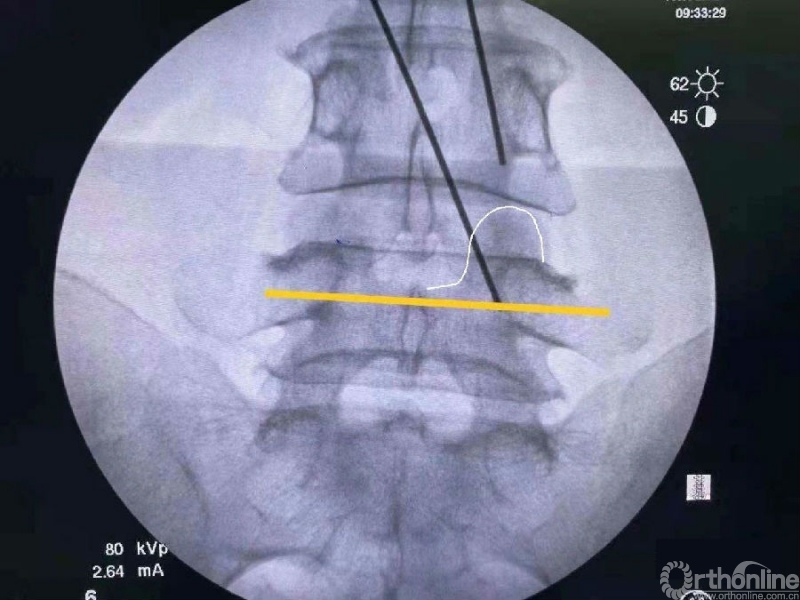

术前克氏针确定内镜口位置位于椎板稍微偏远,是一个比较理想的定位。

我们选用mark磨钻在下关节突上钻孔固定进行透视来确定关节突内缘磨除的外界。

定位磨钻细小,且可立于钻孔内进行透视定位。